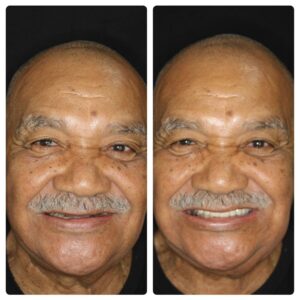

Ter dentes fixos e definitivos;

Deixar sua saúde bucal em dia;

Não fica caindo e soltando;

100% da mastigação de volta;

O implante dura para sempre;

É um tratamento simples;